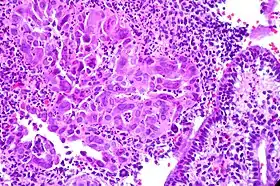

- Зображення цервіциту from the U. of Washington.